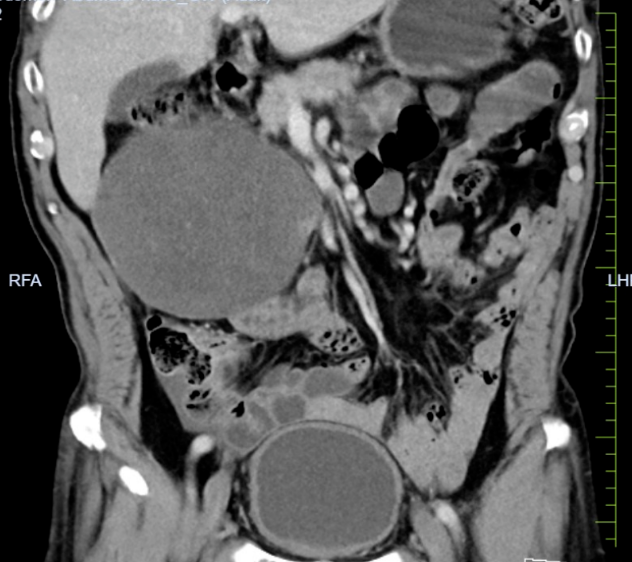

该患者因泌尿系结石于当地医院行CT检查时,发现右中上腹部肠系膜区域存在巨大占位。转入我院后,增强CT检查显示:上腹部肠系膜脂肪间隙内见巨大团块状稍低密度影,病变内可见小血管,且与周围肠管边界不清。尽管患者当时无明显不适症状,但影像学评估提示肿瘤血供极为丰富,并与肠系膜上动静脉关系密切,手术切除难度大,术中面临出血和肠坏死风险。

术后患者清醒拔管,转入ICU监护,次日顺利返回普通病房。在医护团队的精心治疗和护理下,患者恢复顺利,能够正常进食。复查腹部CT证实肿瘤已完整切除。